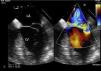

Figure 2.

Two-dimensional transesophageal echocardiogram showing severe mitral regurgitation caused by posterior leaflet prolapse. LA: left atrium; LV: left ventricle.